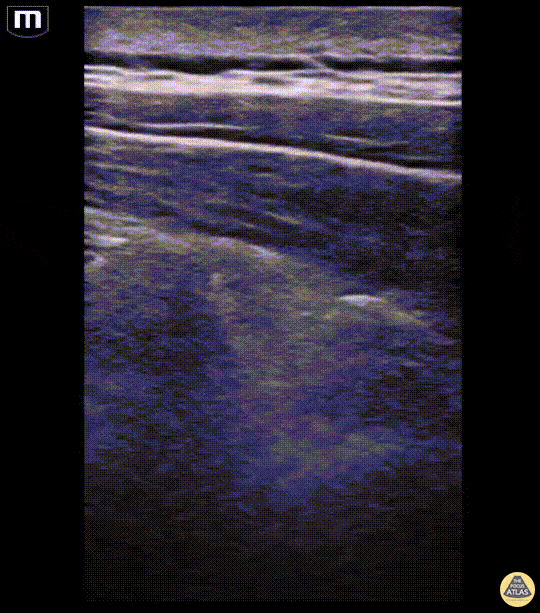

A 45-year-old male presented to the ED as a pedestrian struck by a car. He was hit from behind and pinned to a wall briefly. Workup revealed left sided 1st-5th anterior rib fractures, 3rd-7th posterior rib fractures with significant displacement, as well as left C7 and T1 transverse process fractures and a left medial clavicle fracture. An erector spinae block was performed for analgesia. In the first image, the erector spinae muscle layer can be seen sitting atop two levels of transverse processes. The patient was slowly rolled onto the right lateral decubitus. The second clip shows a needle approaching from cephalad and depositing anesthetic into the fascial plane between the erector spinae and transverse process. The patient felt near immediate pain relief at the termination of the procedure. He was subsequently brought to the SICU prior to having a rib plating operation the following day, and received a serratus anterior catheter placed by anesthesia during pre-op. Dr. Makenna Rice, PGY-1, Denver Health Emergency Medicine Residency Dr. Fred Milgrim, Ultrasound Fellow, Denver Health Emergency Medicine